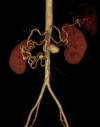

Visceral artery aneurysms are rare, with a 25% rupture risk and an associated 70% mortality. A 55-year-old woman with progressive epigastric pain was found to have multiple large superior mesenteric artery (SMA), branch, and gastroduodenal artery aneurysms along with an occluded celiac artery trunk with hepatic flow dependent on the aneurysm branch. Management included antegrade aortohepatic artery bypass with gastroduodenal artery ligation, followed by SMA stenting and aneurysm coiling. This case is novel, given the diffuse pattern and rarity of SMA and branch aneurysms. This hybrid surgical management highlights innovative strategies to minimize morbidity without compromising definitive treatment of complex visceral artery aneurysms.